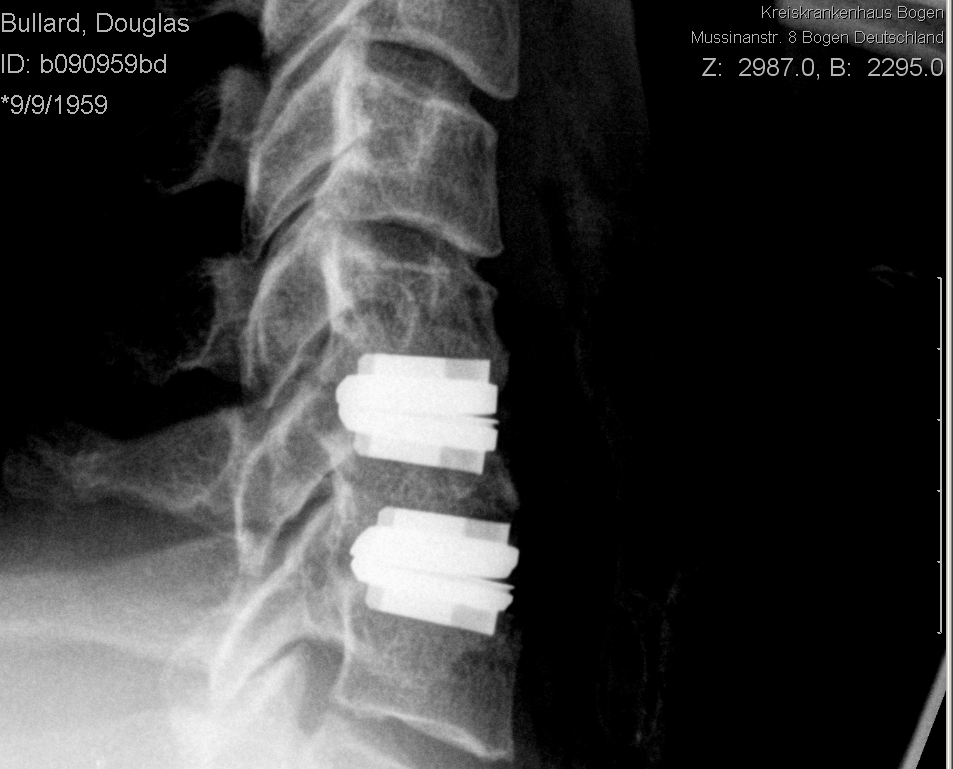

I almost forgot - here’s my X-rays of “after”. Ignore the lean in the forward-facing X-ray - I was doing what my radiologist told me to do, I don’t normally lean like that!

Post op side_sm

Two days after surgery - note that the rather sinister “hooks” at the front of the vertebrae are gone.